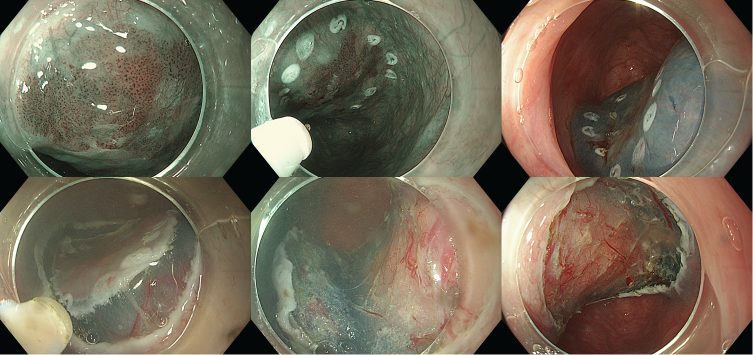

Can thiệp ESD

- Đánh dấu: Dual knife

- Tiêm nâng: Non-lifting sign (-)

- Cắt vòng: Dual knife Cut 2 30W

- Phẫu tích dưới niêm mạc: Dual knife Cut 2 30W + Force coag 30W

- Cầm máu: Soft coag 40W

- Nguồn cắt đốt: Olympus ESG 100

- Thời gian can thiệp: 15 phút

Kết quả sau mô bệnh học sau ESD:

- Carcinoma vảy trong niêm mạc,

- pTis, v0,ly0, HM0,VM0

- Hướng xử trí tiếp theo: Theo dõi